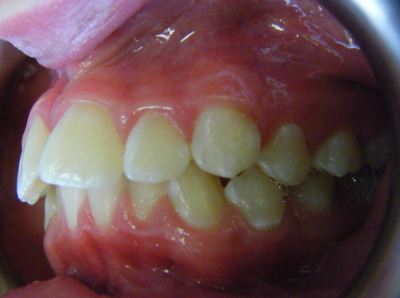

The first two sets of photos below are the before and after photos of a patient who had expansion of the upper jaw followed by upper and lower fixed braces. The third set of photos shows a patient with an expansion plate bonded to the upper teeth and lower fixed braces.